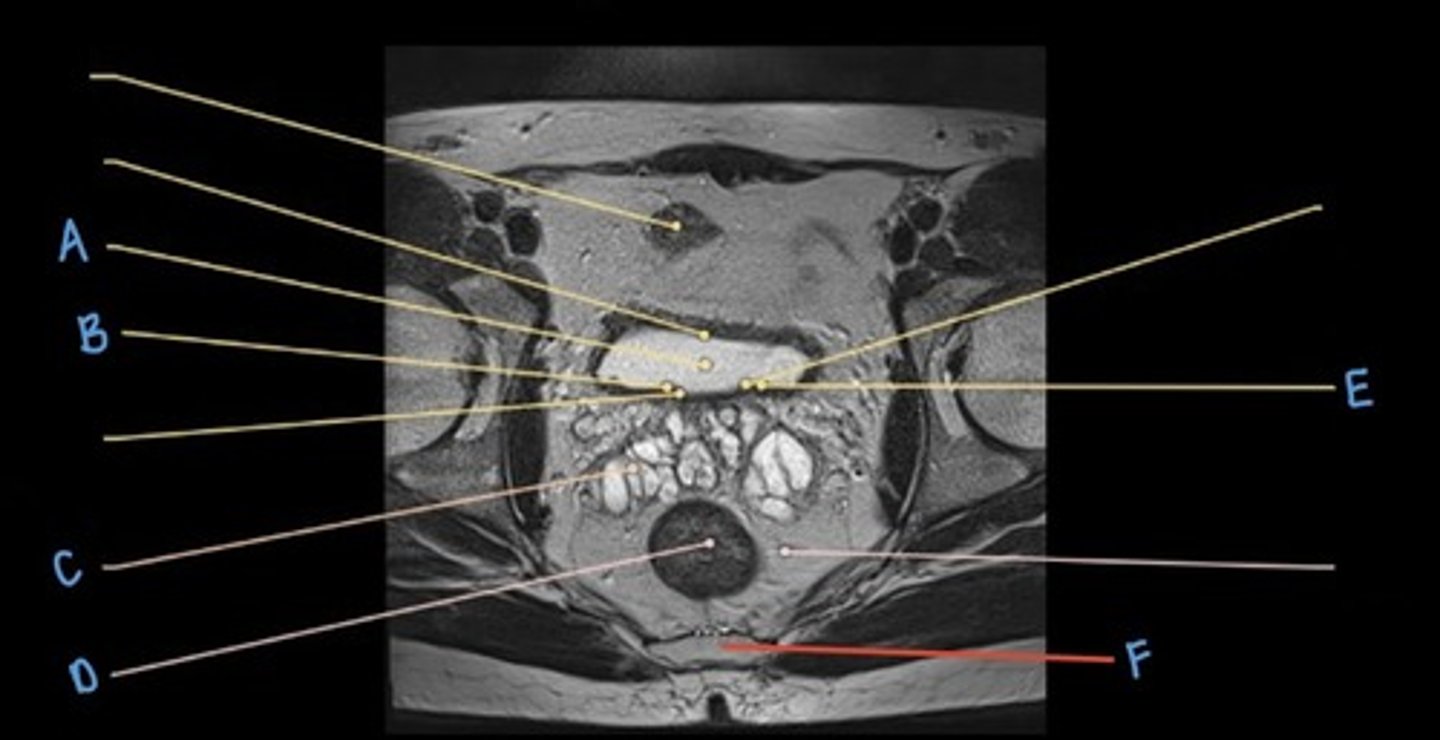

ureter

A & F

small intestine

B

bladder

C

prostate

D

sigmoid colon

E

iliacus muscle

G

psoas major muscle

H